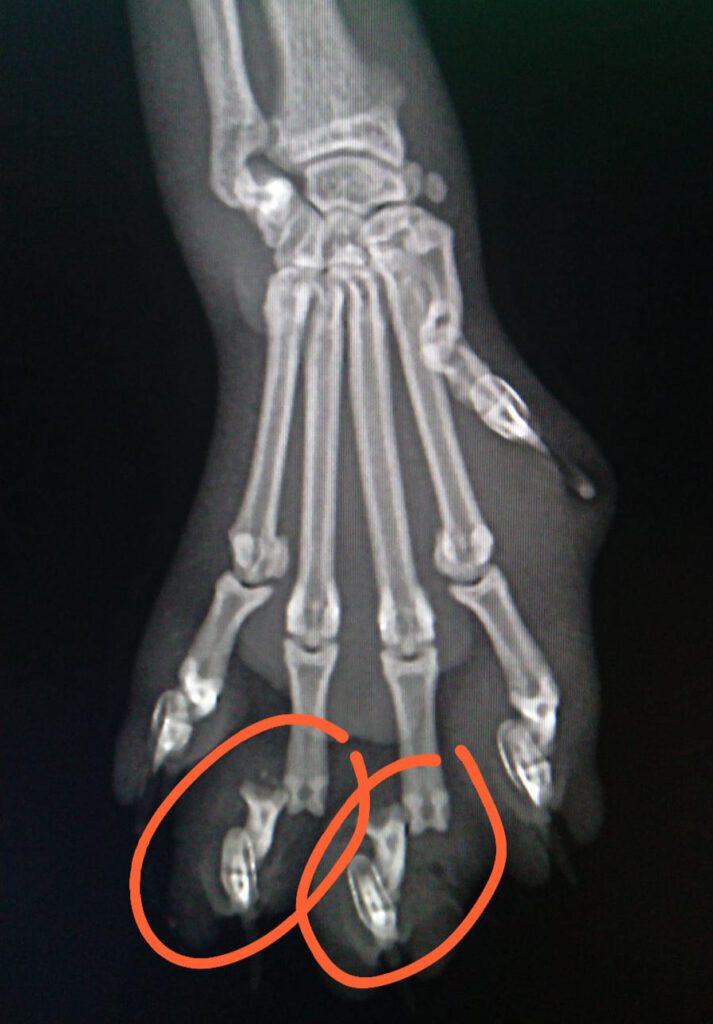

In der anschließenden Behandlung stellte sich heraus, dass die Katze neben erheblichen Verletzungen an der Pfote auch metallische Gegenstände, vermutlich die Befestigung des Köders, in Körper hatte. Die Veröffentlichung der Röntgenbilder wurden vom Tierarzt genehmigt.